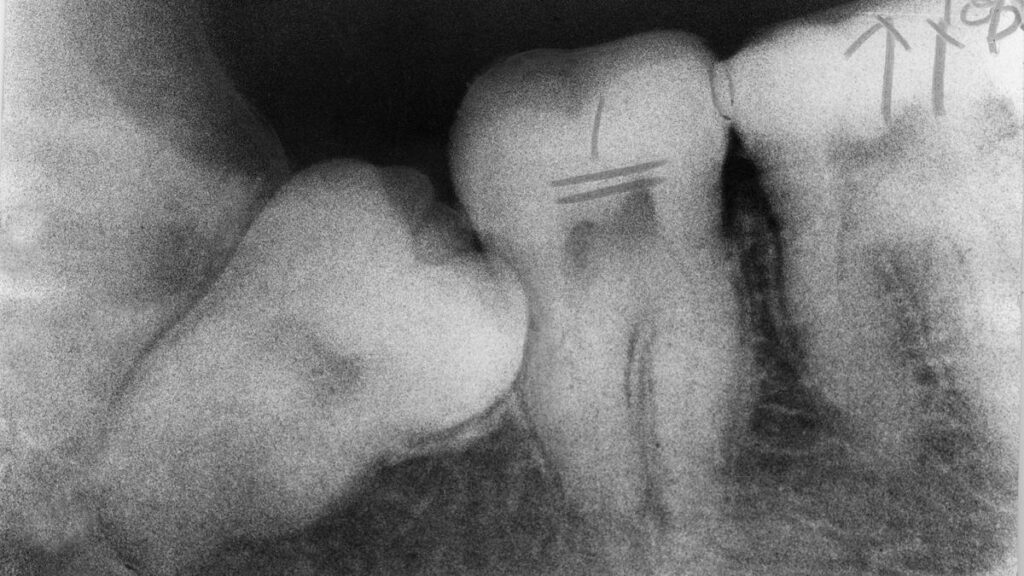

अधिकांश लोग अपने मुंह में बिना दांत दिखाए पैदा होते हैं, भले ही आपके बच्चे के दांत आपके जन्म से पहले ही विकसित होने लगते हैं। जब आप शिशु के दांत आमतौर पर मसूड़ों में चुभने लगते हैं 6 से 8 महीने के बीच. कभी-कभी जब दंत चिकित्सक कैविटी या अन्य समस्याओं की जांच के लिए एक्स-रे लेते हैं, तो वे मसूड़ों के भीतर वयस्क दांतों को उगते हुए देख सकते हैं।